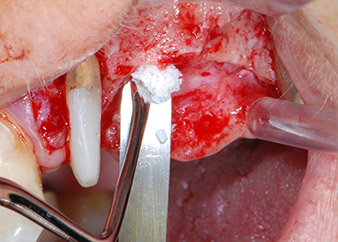

Avant la pose de l'implant, les tissus infectés ont été retirés de l'os alvéolaire sur le site de l'implant et autour des dents piliers à l'aide d'un insert initialement conçu pour le façonnage de l'os et la récupération des copeaux d'os (Piezomed, insert B5) (Figures 6 et 7).

racloir piézoélectrique

Fig. 6 : Le site chirurgical a été débridé à l'aide d'un racloir piézoélectrique conçu pour la collecte des particules d'os et le modelage de l'os.

défauts osseux

Fig. 7 : Après nettoyage, les défauts osseux en position mésiale par rapport à la dent 27 et autour de la racine de la dent 24 étaient nettement visibles.